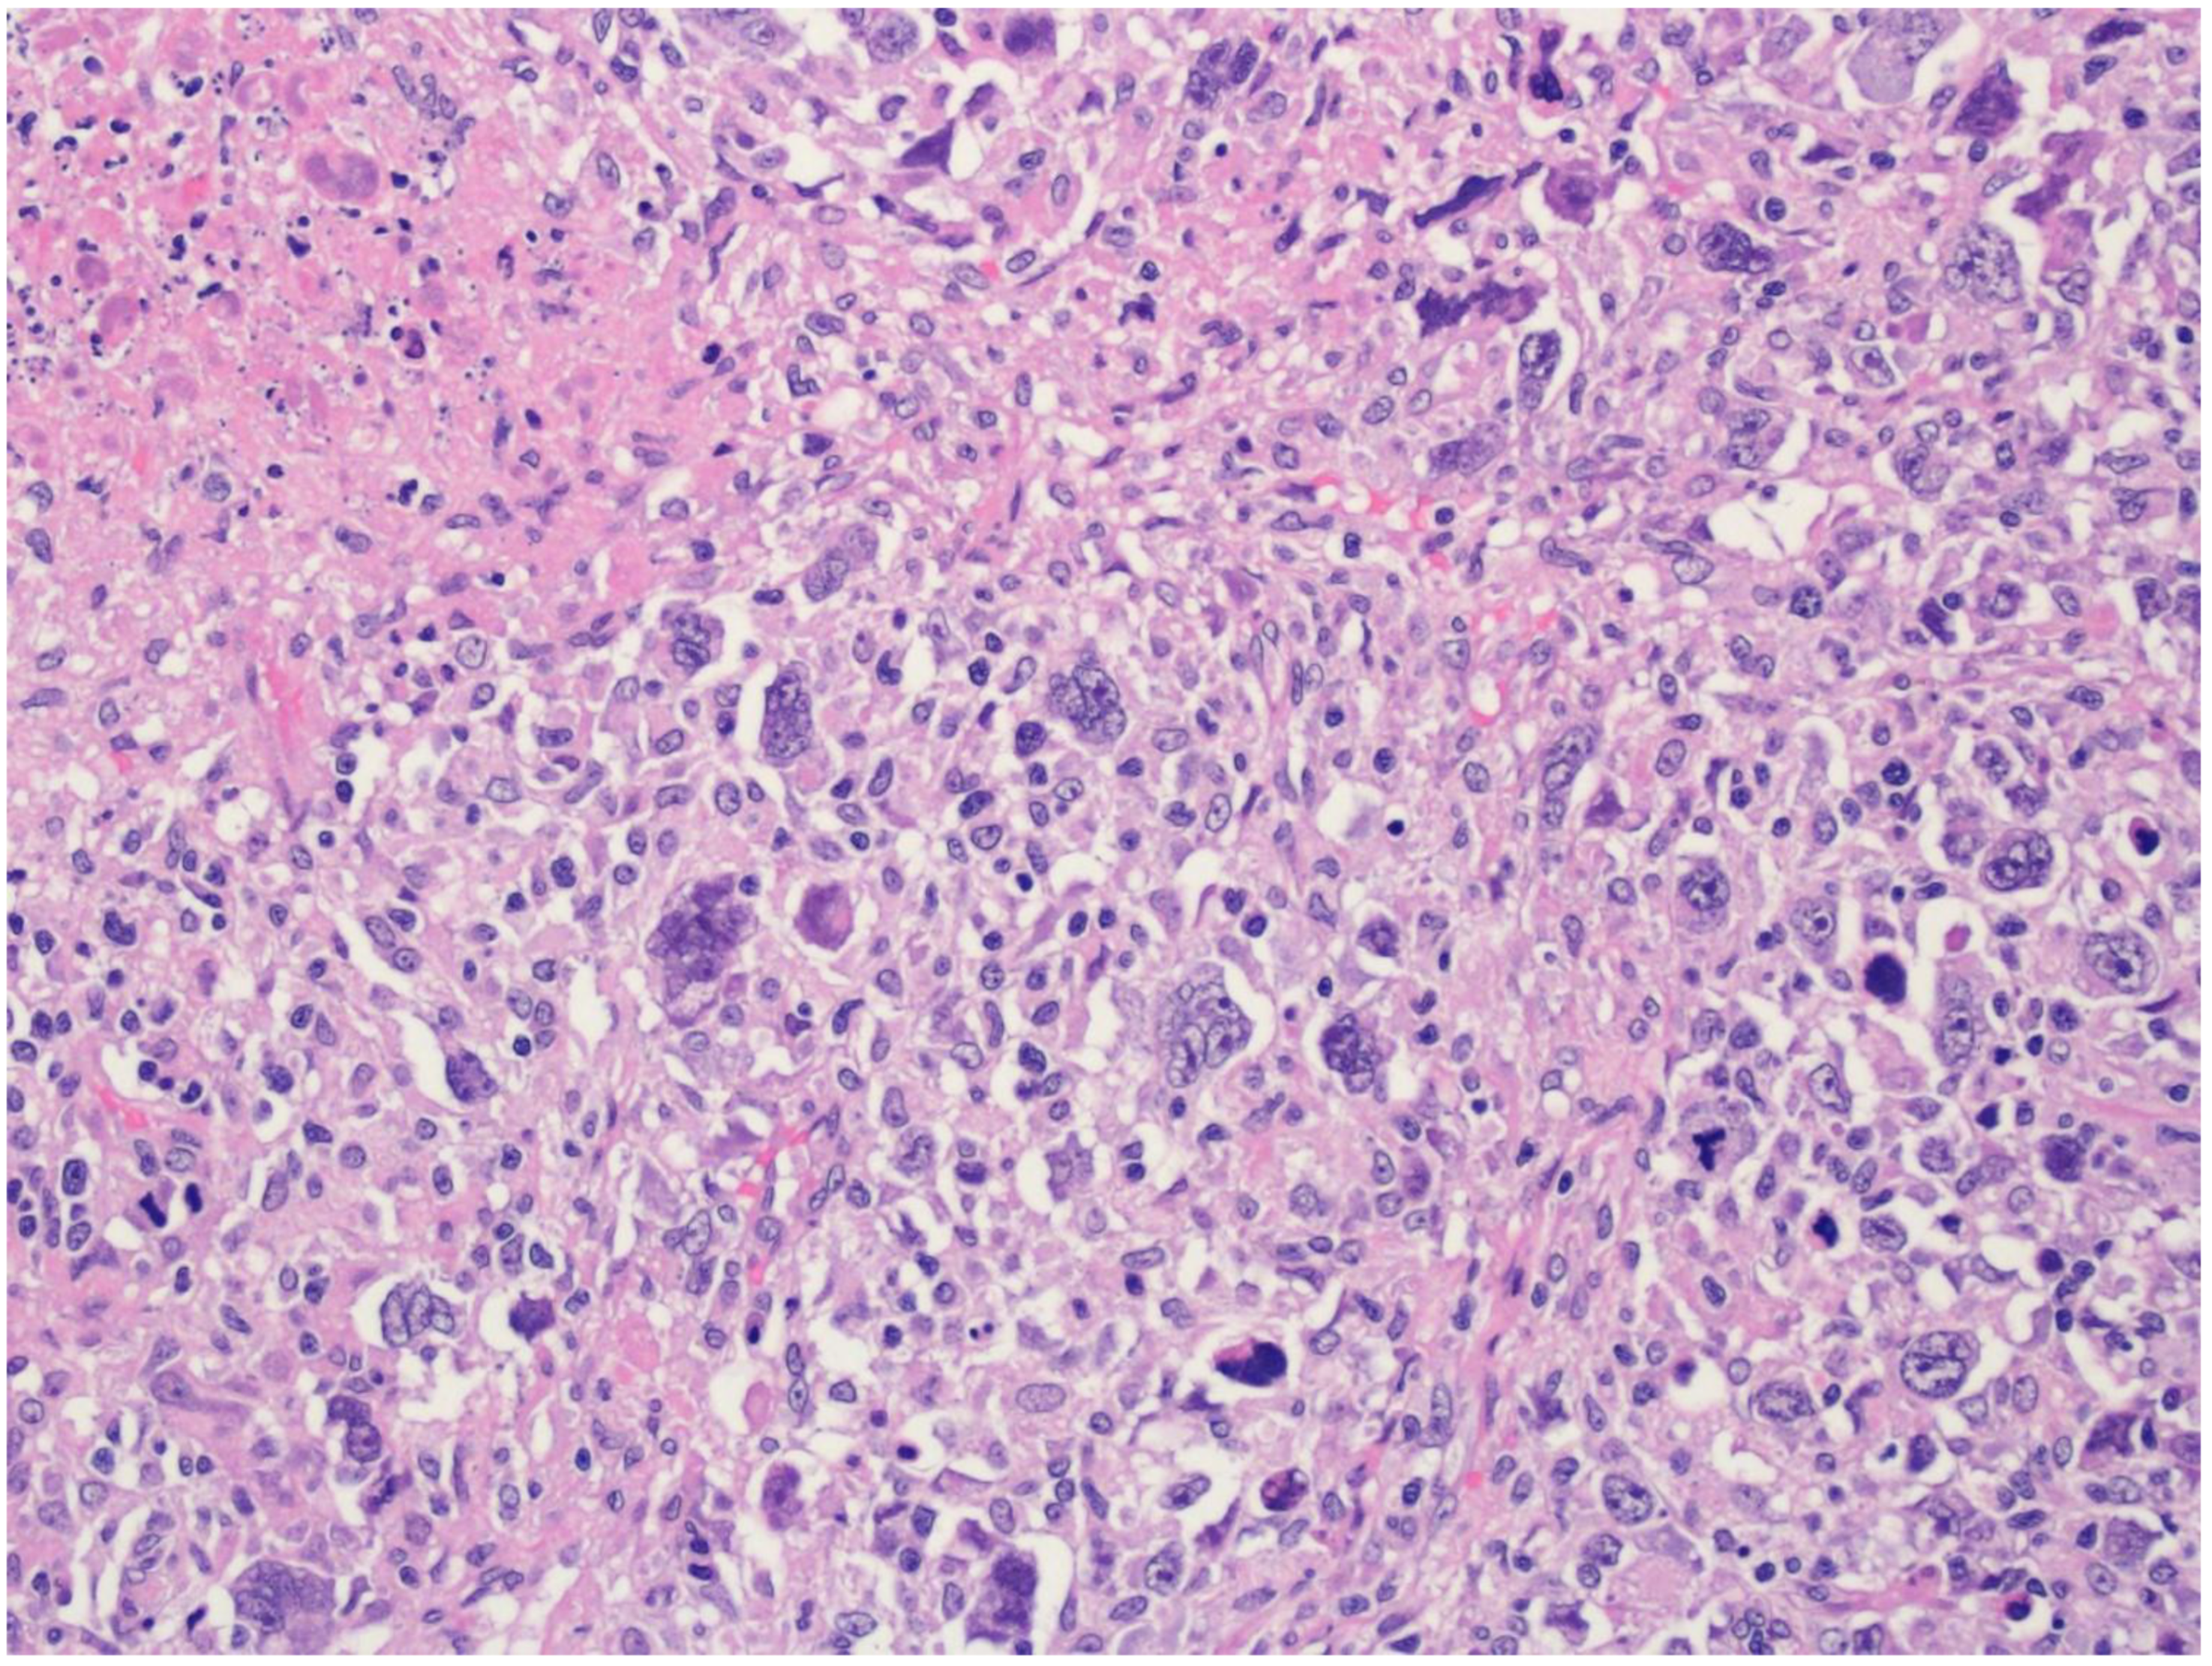

2. Diffuse Large B-Cell Lymphoma, Not Otherwise Specified

4. T-Cell/Histiocyte-Rich Large B-Cell Lymphoma

5. Diffuse Large B-Cell Lymphoma/High-Grade B-Cell Lymphoma with MYC and BCL2 Rearrangements

6. ALK-Positive Large B-Cell Lymphoma

7. IRF4-Rearranged Large B-Cell Lymphoma

8. High-Grade B-Cell Lymphoma with 11q Aberrations

9. Lymphomatoid Granulomatosis

10. EBV-Positive Diffuse Large B-Cell Lymphoma

11. Diffuse Large B-Cell Lymphoma Associated with Chronic Inflammation

12. Fibrin-Associated Large B-Cell Lymphoma

13. Fluid Overload-Associated Large B-Cell Lymphoma

14. Plasmablastic Lymphoma

15. Primary Large B-Cell Lymphomas of Immune-Privileged Sites

16. Primary Cutaneous Diffuse Large B-Cell Lymphoma, Leg Type

17. Intravascular Large B-Cell Lymphoma

18. Primary Mediastinal Large B-Cell Lymphoma

19. Mediastinal Grey Zone Lymphoma

20. High-Grade-B-Cell-Lymphoma, NOS

21. Diffuse Large B-Cell Lymphomas Arising in Immune Deficiency/Dysregulation